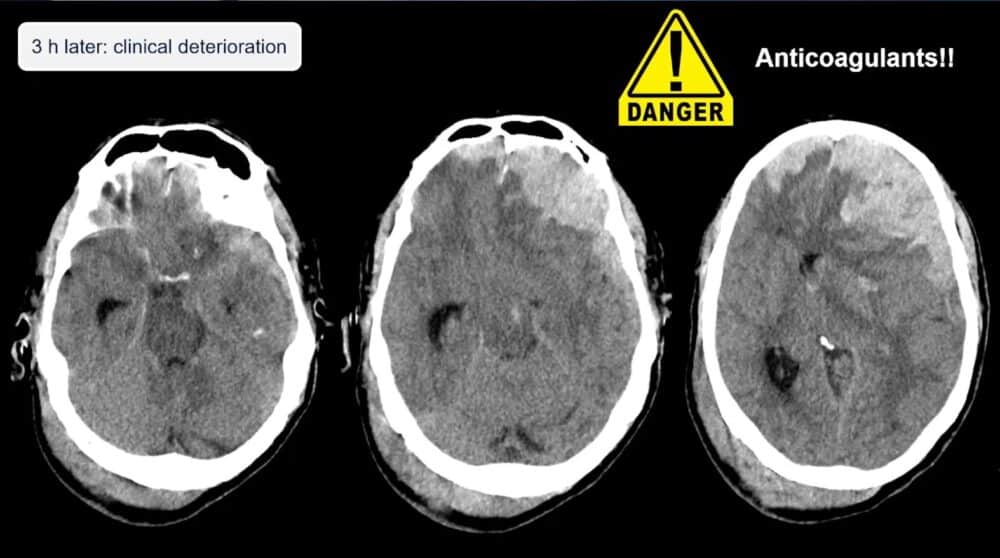

Head injuries also present a significant risk in elderly fall victims, particularly subdural hemorrhages, which are more common due to brain atrophy and anticoagulant use. Even minor head trauma should prompt a CT scan, as elderly patients often show fewer symptoms despite having serious injuries. Referencing the 2023 NICE guidelines, Dr. Blanco Barrio reminded medical professionals that all elderly patients who have experienced head trauma—even those who appear asymptomatic but are on anticoagulants—should undergo a head CT.

“They are at increased risk of hemorrhage in all intracranial compartments,” she noted.